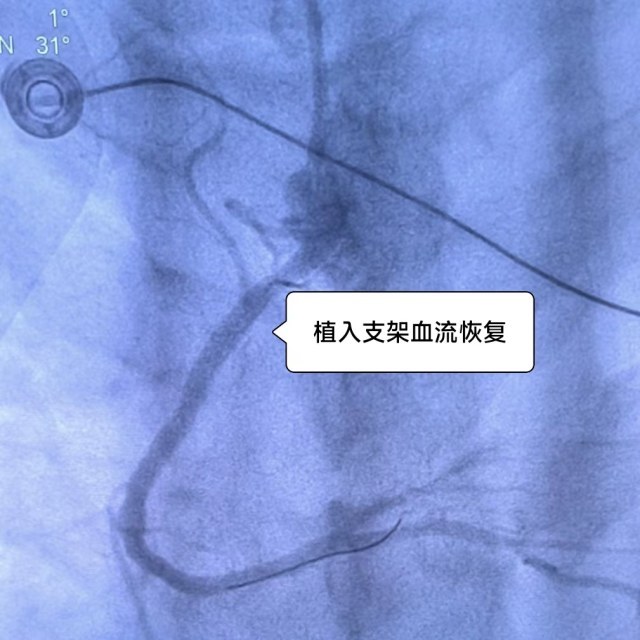

当晚值班的心血管内科医生钱海凭借多年的临床经验,知道刘伟的病情凶险,需要紧急行经皮冠状动脉介入手术(急诊PCI)。果不其然,急诊冠脉造影显示右冠状动脉近段完全闭塞,术中惊险的一幕也让大家都捏了把冷汗。在医生从小伙完全闭塞的血管中抽出大量血栓的时候,刘伟突发心跳骤停、室颤,在医护人员除颤后心跳恢复,立马进行了支架植入,术后刘伟的右冠状动脉血流恢复,有惊无险!患者从鬼门关走了一趟!“心梗越来越年轻化,控制体重,戒烟控制血压,刻不容缓!”钱海在术后反复叮嘱。